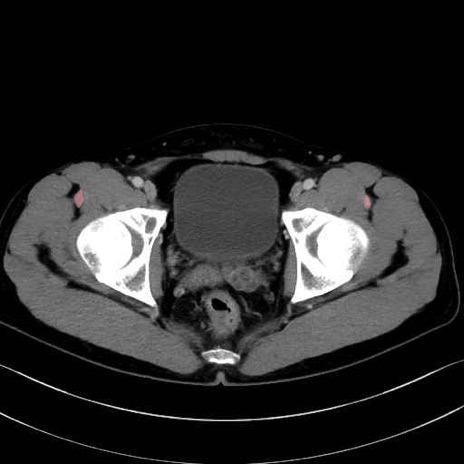

2. 腸腰筋群と骨盤底筋

大腰筋 (Psoas major)

腸骨筋 (Iliacus)

肛門挙筋 (Levator ani)